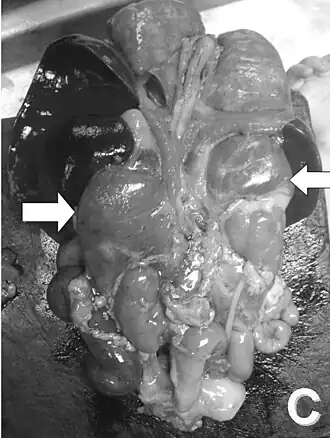

Вскрытие новорождённого. Стрелками указаны увеличенные надпочечники